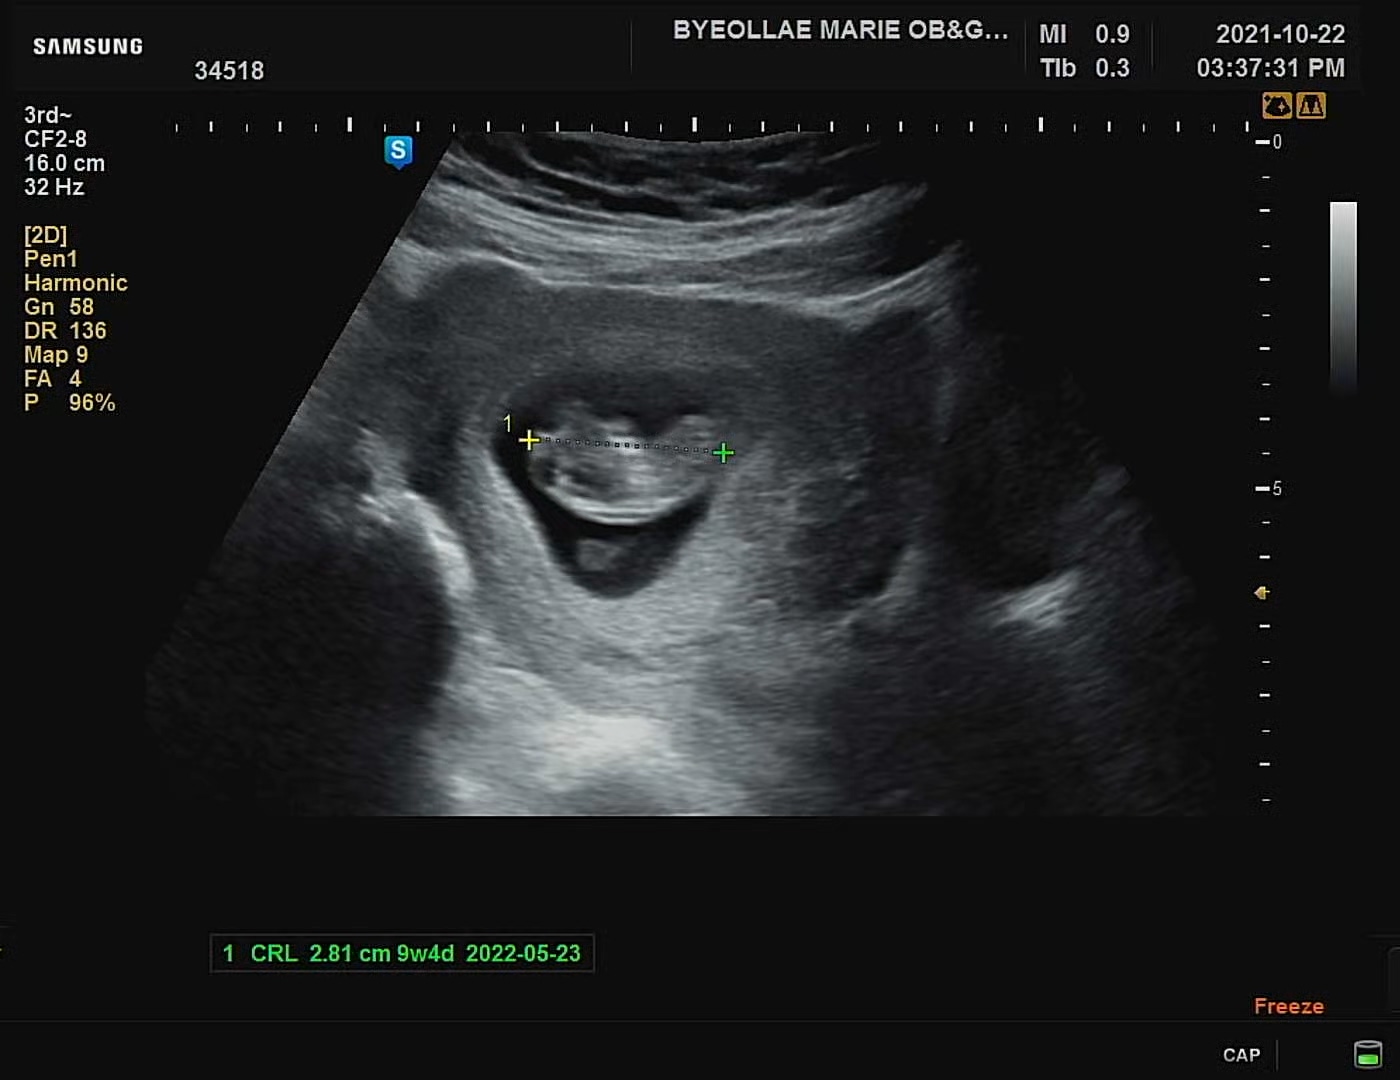

저번 주 금요일 9주 차 5일 되는 날 초음파 검사를 하였다. 이번 까꿍이 심박수는 170으로 건강하며, 몸 전체 길이는 3cm이다. 9주 차 때는 일반적으로 2.3~3cm 정도 된다고 하는데 다행히 알맞게 잘 성장하고 있다.

심박수 사운드가 커진듯한 느낌적인 느낌! 현재도 난황을 통해서 영양소를 공급하고 있다. 초음파 영상의 아기 아래쪽에 동그라미가 난황이다.

초음파 검사를 하는 동안 마치 우리를 보고 만기든 몸을 활짝 폈다 접었다하는 까꿍이. 건강하고 활발하게 자라나고 있다. 엄마, 아빠 까꿍이 보러 온 줄 알고 착하게 움직이며 인사해주네. 헤헷 다음 검사는 12주 차 시기로, 기형아 검사 1차를 하는 때이다.

까꿍이의 9주차 5일째의 초음파 영상 기록. 2주 뒤에 또 보자 까꿍아♥